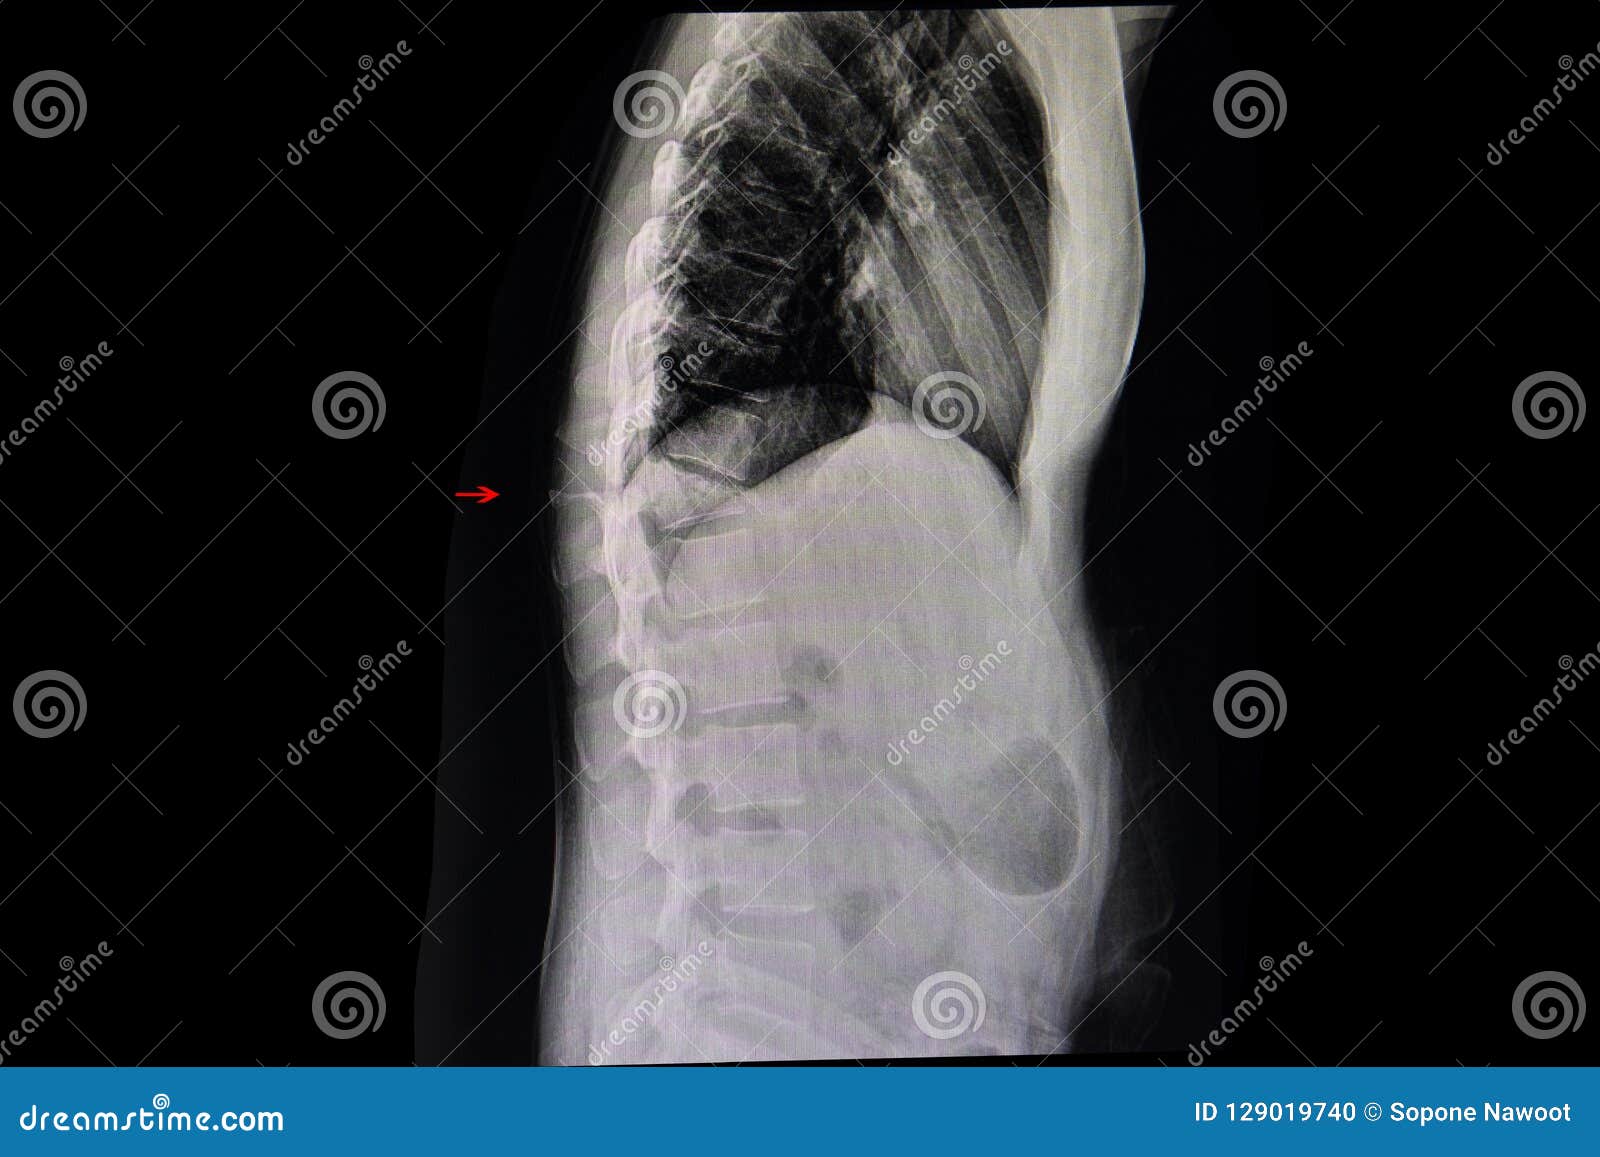

Frattura Di Compressione Di Una Spina Dorsale Toracica Della Spina Dorsale Fotografia Stock Immagine Di Rappresentazione Anatomia